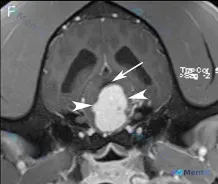

今天整理了一个挺有警示意义的病例——影像读片时的解剖定位真的是「差之毫厘,谬以千里」。 先看原始影像信息 这是一张脑部横断面增强后 T1WI 图像: - 可见一较大的显著强化髓内占位,使脑干扩张; - 病灶周围有水肿; - 中脑导水管被背侧推挤并受压; - 侧脑室轻度不对称扩张。 分析前先踩个「坑」...